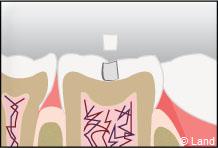

Un inlay reconstitue l’anatomie dentaire en comblant une cavité taillée dans la dent.

L’inlay-onlay reconstituera la dent comme la dernière pièce d’un puzzle. Il sera véritablement collé dans la dent.